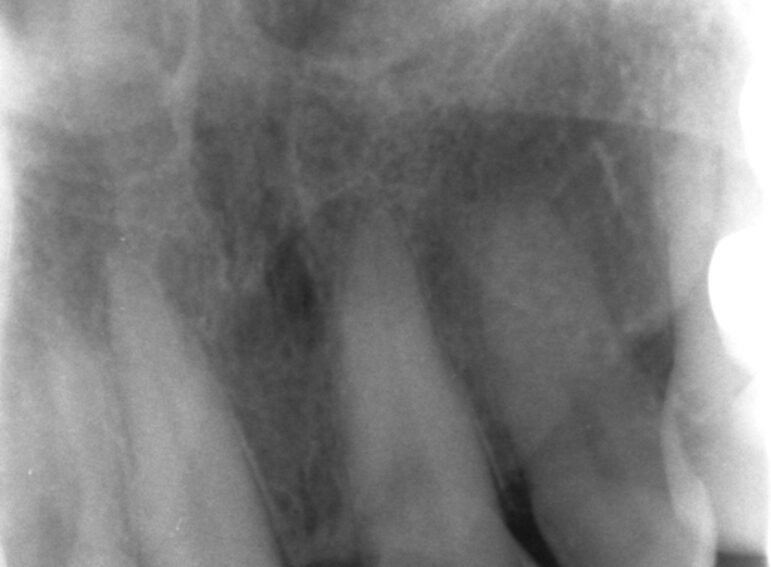

Case 22 – Endodontics

Unsavable External Cervical Resorption